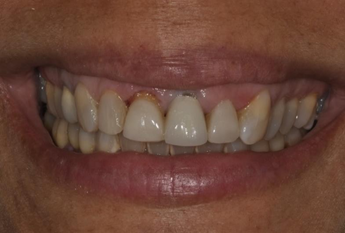

Patient I. A., female, 47 years old, attended the dental office with the chief complaint of dissatisfaction with her anterior teeth and smile. On clinical examination a ceramic veneer was found on tooth 11 with altered color, irregular shape and contour, and on tooth 21 an all-ceramic crown with altered color was found. Both restorations had different colors and volumes, as well as the gingival apex on both teeth was discrepant (Figures 1-3).

Figure 1 Initial photograph showing the discrepancy in color, shape and size between the restorations.

Figure 1 Initial photograph of the smile.